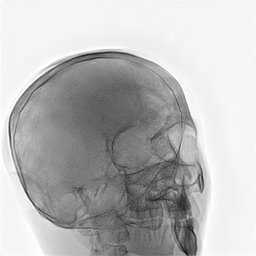

Refer to caption

Figure 1: Overview of MedShift inference. A source image x1x_{1} is first encoded into a domain-agnostic latent representation zτz_{\tau}. This latent lies near a shared manifold across all domains. Then, translation is performed by forward-time sampling conditioned on the target domain label to obtain the translated image x^1\hat{x}_{1}.

During inference, a source image, such as a simulated X-ray (class S), is first encoded into a domain-agnostic latent representation via time integration. Starting from the observed image x1x_{1}, we integrate backward from t=1t=1 to an intermediate time τ(0,1)\tau\in(0,1) under the source domain condition c=Sc=S, yielding the latent representation zτz_{\tau}:

zτ=x1τ1vθ(xt,c=S,t)dt.z_{\tau}=x_{1}-\int_{\tau}^{1}v_{\theta}(x_{t},c=S,t)\,dt. (1)

This intermediate state lies in a shared latent manifold that is approximately aligned across all domains, as shown in Section B. To generate the translated image in a target domain, e.g., a real X-ray at high dose, we then integrate forward from τ\tau to 11, this time conditioning the target domain c=Rc=R:

x^1=zτ+τ1vθ(xt,c=R,t)dt.\hat{x}_{1}=z_{\tau}+\int_{\tau}^{1}v_{\theta}(x_{t},c=R,t)\,dt. (2)

This two-stage process, consisting of encoding and translation, enables faithful domain transfer while preserving essential anatomical content. Figure 1 illustrates this conditional transport mechanism between domains.